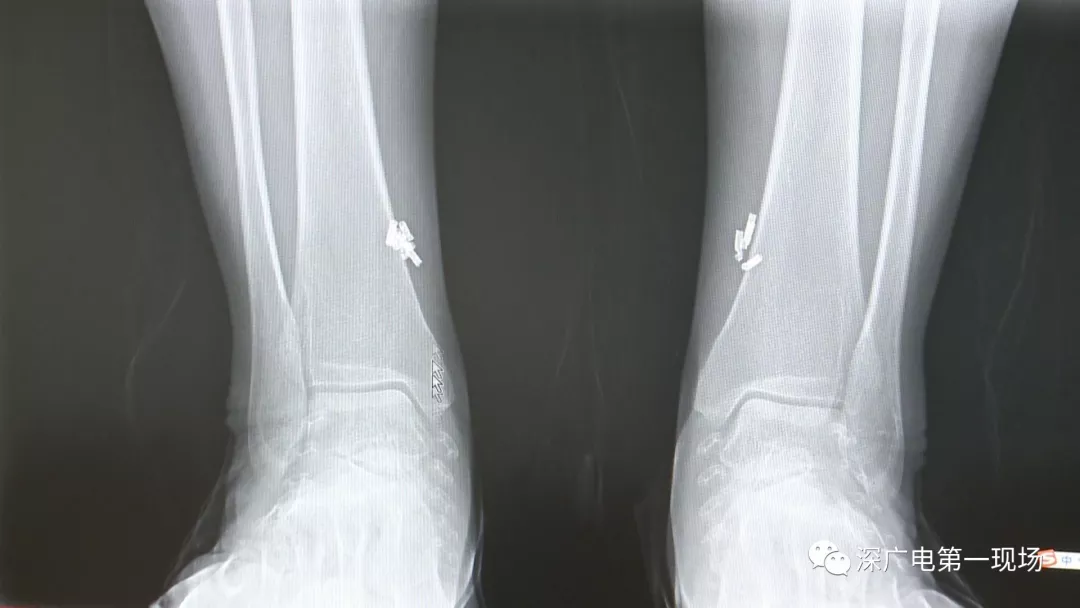

深圳一女子全身被植入彈簧圈,數(shù)量多到驚人!竟是為治這病…

出于保護(hù)患者,我們沒有直接采訪,但是通過醫(yī)生的介紹,記者了解到,病人是個(gè)36歲的女性,2歲開始就有癲癇病史,而且藥物治療也并不見效。

多方打聽之后,在山東某診所用全身埋彈簧圈的方式治療癲癇。陶主任介紹,這樣的方式想要治愈,那幾率也等同于撞大運(yùn)??!